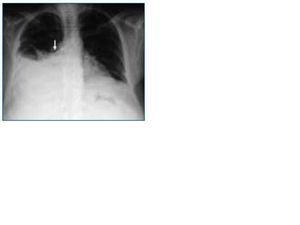

A los 29 días, la paciente acude a hemodiálisis refiriendo disnea y dolor escapular derecho. Al iniciar la sesión, se extrajo líquido claro por la rama arterial y hemático por la venosa. La radiografía de tórax urgente (fig. 1) mostró derrame pleural derecho. Se extrajeron 700 cc de líquido claro a través de la rama arterial (seroma) y se retiró el catéter. La paciente fue dializada sin heparina a través de un catéter femoral derecho. A los 15 minutos de finalizar la hemodiálisis la paciente inició un cuadro súbito de dolor costal derecho, disnea, sufriendo una parada cardiorrespiratoria. La exploración física reveló hipoventilación pulmonar derecha. La analítica mostró descenso de la hemoglobina y la radiografía de tórax opacidad pulmonar derecha completa. Con la sospecha de hemotórax masivo se colocó un tubo de tórax y se iniciaron maniobras de resucitación. La paciente fue trasladada a la UVI donde permaneció 72 horas, pasando posteriormente a nuestra Unidad de Hospitalización sin secuelas.

Figura 1.